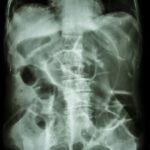

Jejunal Atresia is a birth defect in a newborn characterized by the partial or complete absence of the membrane connecting the small intestines to the abdominal wall (the mesentery). It causes a portion of the small intestines (the jejunum) to twist around an artery that supplies blood to the colon (the marginal artery). This leads to an intestinal blockage or “atresia.” Common symptoms in the newborn include feeding difficulties, failure to thrive, vomiting bile (a yellowish-green fluid), abdominal swelling, and/or absence of bowel movements after birth. It typically occurs sporadically in people with no family history of the condition; however, more than one family member can rarely be affected, suggesting that there may be a genetic component in some cases. Jejunal atresia is typically treated with surgery.

Jejunal atresia occurs when the membrane that attaches the small intestines to the abdominal wall (called the mesentery) is partially or completely absent. As a result, a portion of the small intestines (the jejunum) twists around an artery that supplies blood to the colon (the marginal artery). This leads to an intestinal blockage or “atresia.”